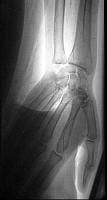

问题 43岁女性患者,突发左手疼痛伴多个指头麻木就诊,行左上肢动脉照影,示左侧桡动脉广泛的充盈缺损,结合临床考虑左侧桡动脉病变为 ( )

选项 A、桡动脉血栓形成 B、桡动脉假性动脉瘤 C、桡动脉炎 D、桡动脉真性动脉瘤 E、桡动脉夹层

答案 A